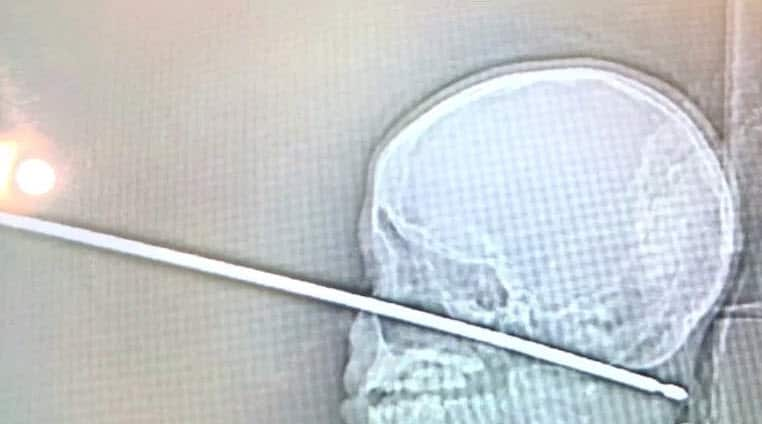

X-ray of a skewer that pierced the skull of Xavier Cunningham. Source: Fox4 TV

But miraculously, that's where Xavier Cunningham's bad luck ended. The skewer had completely missed Xavier's eye, brain, spinal cord and major blood vessels, The Kansas City Star in Missouri reports.

Xavier's harrowing experience began on Saturday afternoon when yellow jackets attacked him in a tree house at his home in Harrisonville, about 56km south of Kansas City. He fell to the ground and his mother, Gabrielle Miller, ran down the stairs when she heard screaming. His skull was pierced from front to back with 15cm of skewer still sticking out of his face.

There was no active bleeding, allowing the hospital time to get personnel in place for a removal surgery on Sunday morning that was complicated by the fact that the skewer wasn't round. Because it was square, with sharp edges, it would have to come out perfectly straight. Twisting it could cause additional severe injury.